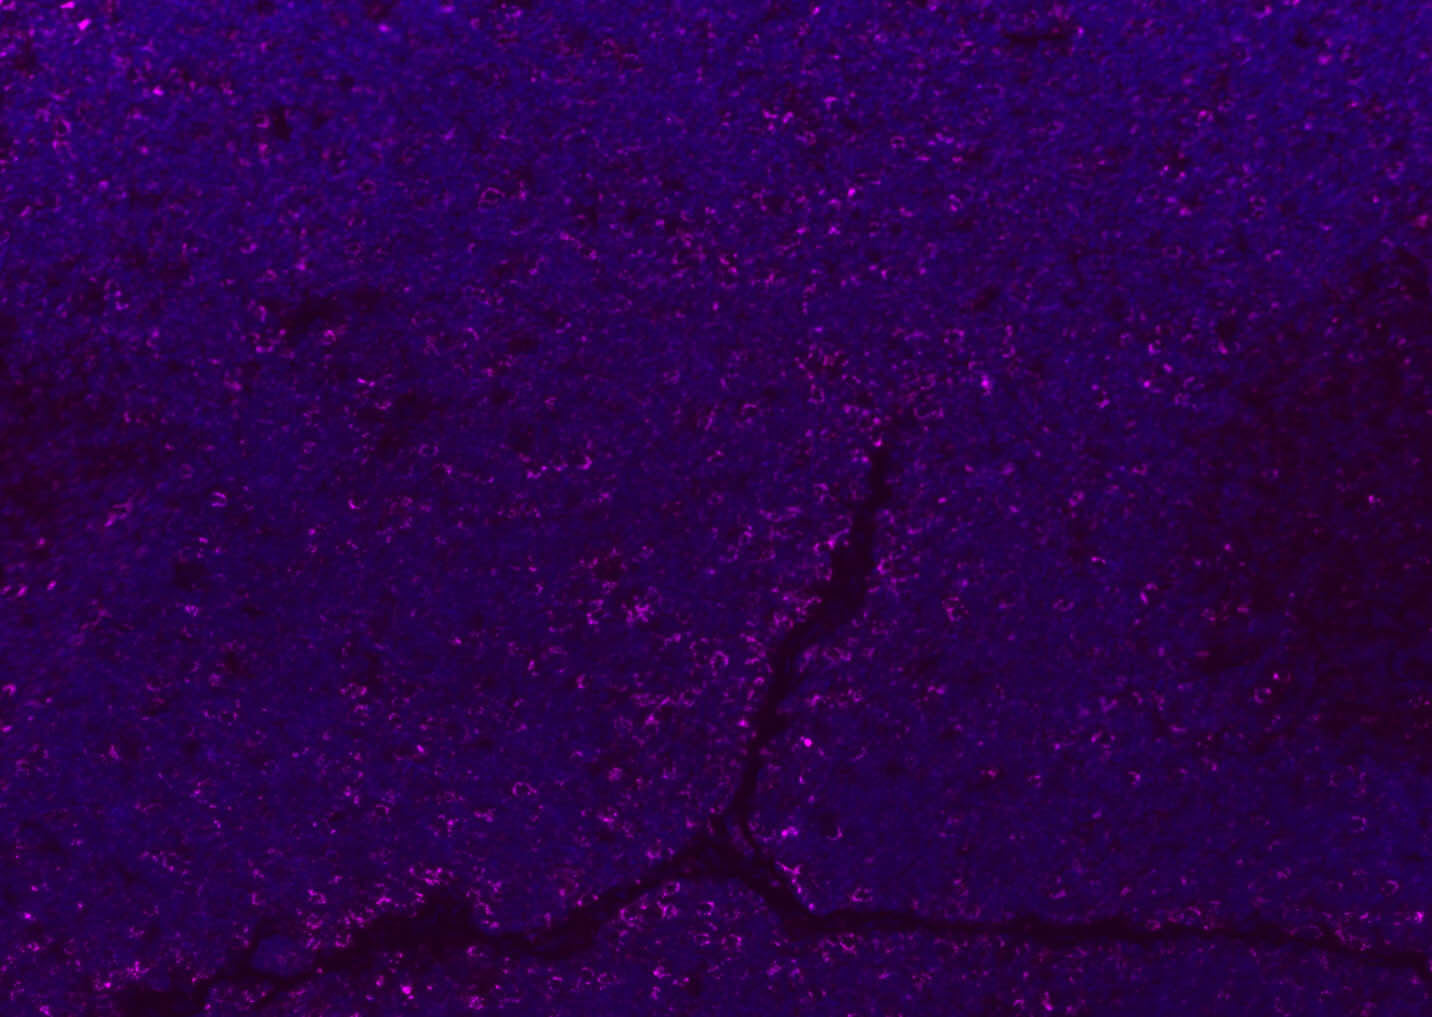

Paraformaldehyde-fixed, paraffin embedded (rat lymphoid); Antigen retrieval by boiling in sodium citrate buffer (pH6.0) for 15min; Blocking buffer (normal goat serum) at 37°C for 30min; Antibody incubation with (CD8B) Polyclonal Antibody, Unconjugated (bs-4914R) at 1:200 overnight at 4°C, followed by a conjugated Goat Anti-Rabbit IgG antibody (bs-0295G-AF488) for 90 minutes, and DAPI for nuclei staining.